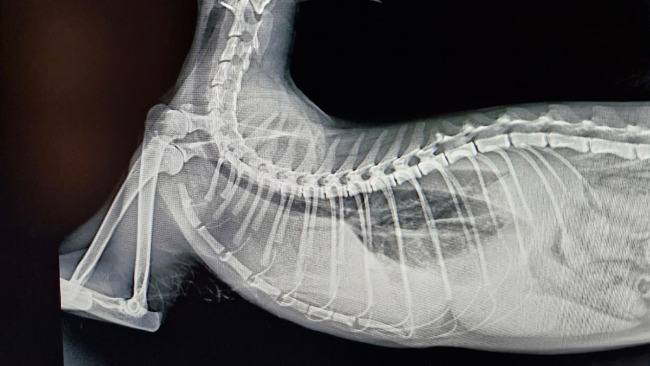

Jest to bardzo poważna choroba, wywołana mutacją koronawirusa, której brak leczenia skutkuje bardzo niską przeżywalnością – od kilku dni do kilku miesięcy. Atakuje ona narządy wewnętrzne, a u naszej kotki, która cierpi na postać wysiękową, głównie objawia się gromadzeniem płynów w klatce piersiowej. Jest to trudna choroba do wyleczenia, lecz dzięki nowoczesnym terapiom istnieje szansa na uratowanie życia kotki.

Zdjęcie RTG zalanych płuc oraz płynu, który został sciągnięty za pomocą punkcji (28.12.2024)